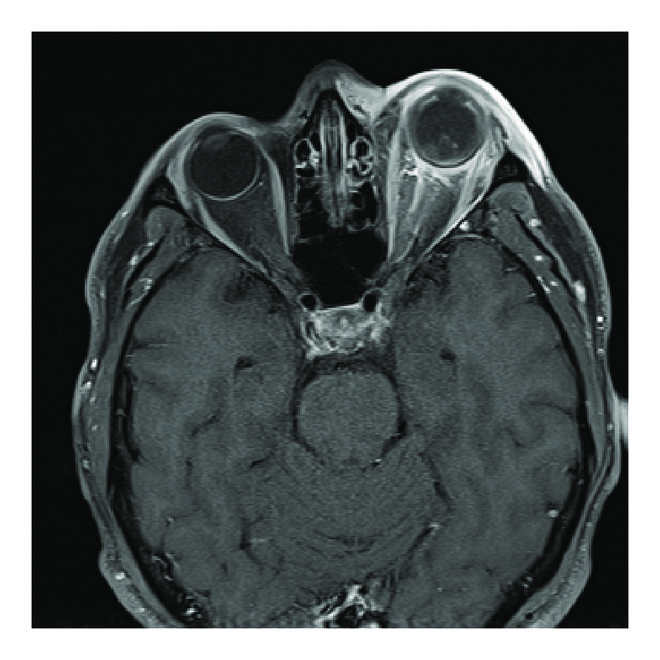

Due to the keratitis and scleral involvement the patient was empirically started on intravenous vancomycin and started on fortified vancomycin and tobramycin ophthalmic drops every hour. MRI of the orbits, obtained less than 24 hours after initial presentation, demonstrated spontaneous dislocation of the native intraocular lens posteriorly into the vitreous with scleral enhancement along the inner walls of the left globe and enhancement was noted along the left optic nerve in the orbital apex extending through the optic canal to the prechiasmatic optic nerve (Figures 1(d) and 1(e)). Neurosurgery was asked to evaluate the patient and felt there was no indication for intracranial surgery at that time.